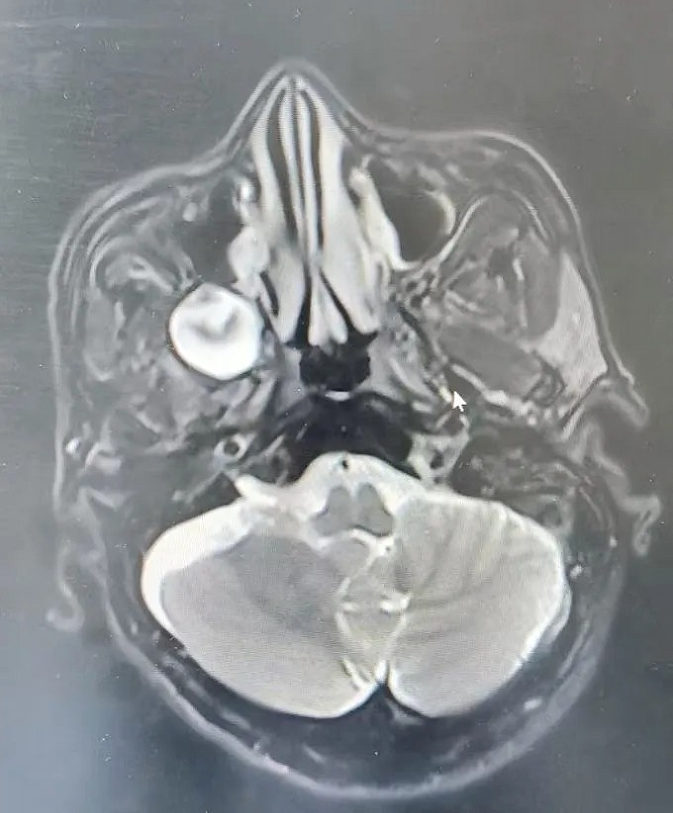

55岁的张先生,因右侧头痛持续2个多月,前往浙大邵逸夫阿拉尔医院耳鼻咽喉头颈外科就诊。经医生详细检查,发现患者翼腭窝内有囊实性占位,大小约2.3×2.2 cm,初步判断为翼腭窝神经鞘瘤。翼腭窝神经鞘瘤起源于翼腭窝内的神经鞘细胞,此区域解剖位置深且周围结构复杂,手术难度极大,为解决患者的痛苦,耳鼻咽喉头颈外科团队决定积极准备,全力保障手术成功。

医院耳鼻咽喉头颈外科医疗团队在术前对患者进行了全面评估,综合考虑患者年龄、身体状况及肿瘤大小等因素,制定了精准详细的手术方案。手术采用经鼻内镜泪前隐窝入路,这一选择确保了在手术过程中能更好地暴露肿瘤,为彻底切除提供了有利条件。